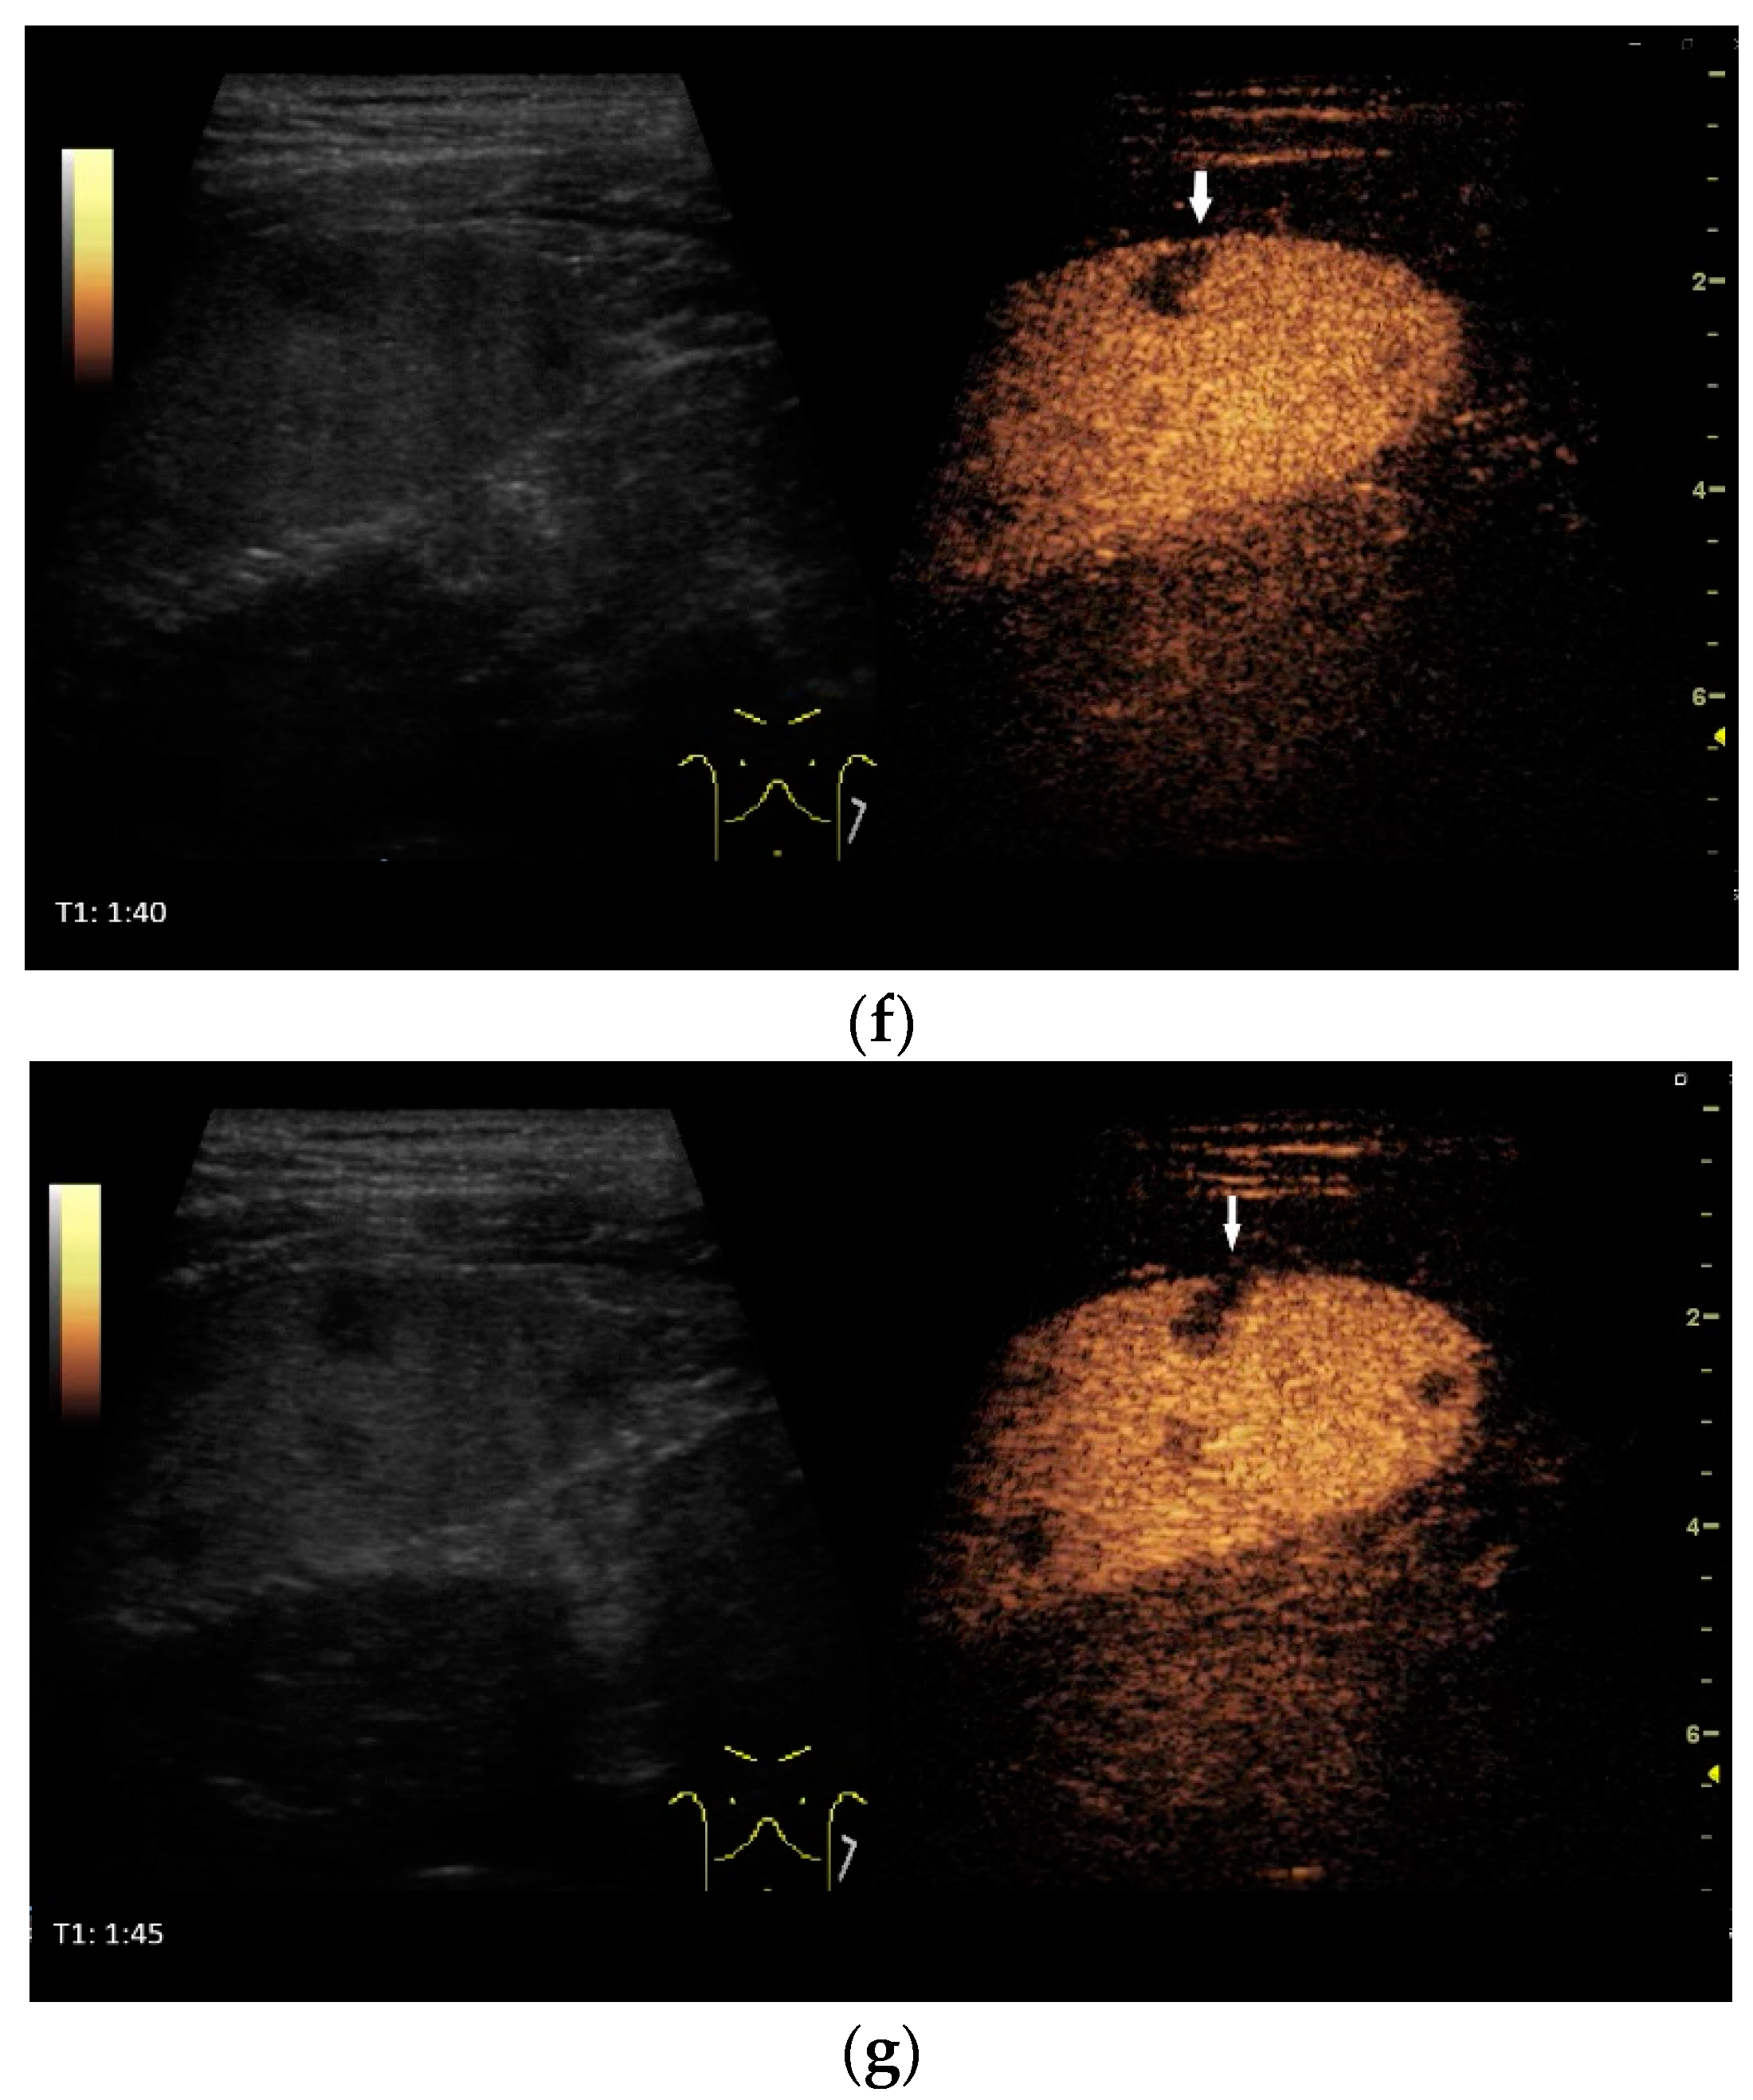

9. Spleen

Spleen involvement usually only occurs in disseminated disease. The manifestations are splenomegaly, hypoechoic micronodular (miliary), or macronodular lesions [8,74], as well as splenic abscesses [75] [Figure 4a–d]. In a group of patients with tuberculosis and mostly advanced HIV infection, 37% had splenic lesions [5]. In 33%, splenic lesions were associated with lymphadenopathy, and 16% each had splenic lesions and ascites or splenic lesions, ascites, and lymphadenopathy. Micronodular lesions may be indistinguishable. If this is suspected, examination with a high-resolution linear transducer is recommended. Using CEUS, splenic lesions in the arterial phase showed a hyperenhancement, followed by either a slow washout or a persistent enhancement in the middle and late parenchymal phase [76]. A fast washout was the exception, but nevertheless was also possible. These exceptional cases would therefore be difficult to differentiate from malignancies. There was also rim-like enhancement with central nonenhancement, like abscesses and septation-like enhancement [76]. Another study using CEUS in splenic manifestations of tuberculosis presented homogeneous enhancement (6.7%), heterogeneous enhancement (63.3%), and nonenhancement (30.0%). Most of the cases showed low enhancement. Among these cases, heterogeneous enhancement was divided into septal enhancement type (21.1%) and marginal enhancement type (78.9%) [77] [Figure 4c–g]. The most important differential diagnoses are non-Hodgkin’s lymphoma and other granulomatous inflammations, such as sarcoidosis, especially in the presence of lymphadenopathy. The splenic lesions must be differentiated from mycotic abscesses, leukemic infiltrates, and metastases. In the meta-analysis conducted by van Hoving et al. [78], splenic lesions as manifestations of abdominal tuberculosis had a broad sensitivity of 13–62% in five studies using B-mode ultrasonography. The specificity was higher, at 86–100%.

Figure 4.

Sonographic and CEUS features of splenic tuberculosis. Sonographic and CEUS features of splenic tuberculosis. Subcapsular splenic lesion (arrow) (a), subcapsular splenic lesion using a linear transducer of 12 MHz (arrows) (b). Histologically confirmed tuberculosis from mediastinal lymph nodes. Multiple small splenic lesions (c). Using CEUS with a linear transducer (9 MHz), these are slightly hypoenhanced in the arterial phase (d), and show a progressive washout in the course of the venous phase (arrows) (e). Subcapsular splenic lesion (arrow) with nonenhanced and hypoenhanced parts and hyperenhanced rims indicate a caseous necrosis (f). In another section, an interrupted spleen capsule (arrow) due to a rupture of the caseous necrosis can be assumed (g).